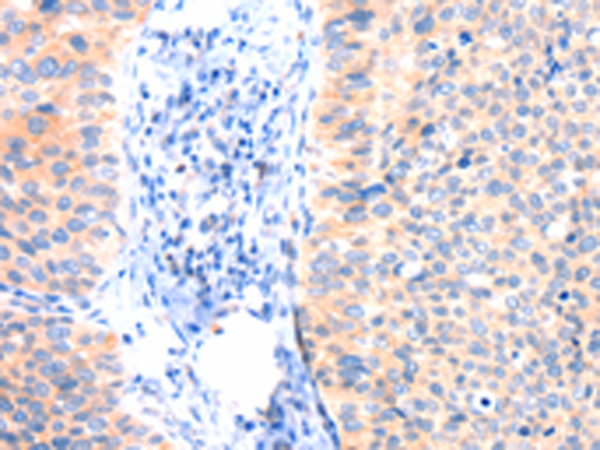

分类: 科研抗体货号: P04759别名: 1F5; EJ16; EJ30; EL32; G344; MIN1; MIN2; MIN3; MIRL; HRF20; MACIF; MEM43; MIC11; MSK21; 16.3A5; HRF-20; MAC-IP; p18-20应用: WB,IHC反应种属: Human